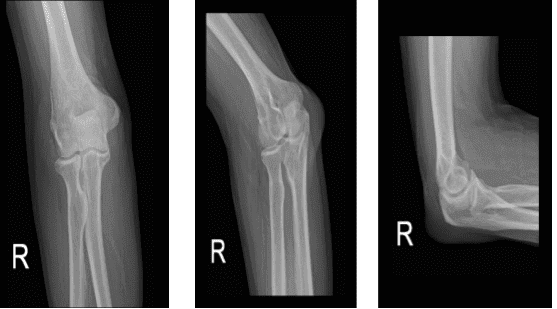

A 65 year-old male patient is here with X-rays of his right elbow and complains of pain from his right elbow. He is unsure how it happened but he said he started to feel the pain 2 days ago. According to his X-ray he has right olecranon bursitis with increased temperature and redness.

Right elbow x-ray